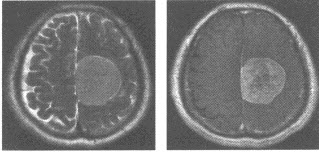

男性,58岁,右侧肢体活动不灵2个月,加重半月余。查体:右侧肢体肌力4级,病理征(-)。MRI平扫T

2

WI及增强扫描如图,最可能的诊断为()

A:脑转移瘤

B:胶质瘤

C:海绵状血管瘤

D:淋巴瘤

E:脑膜瘤